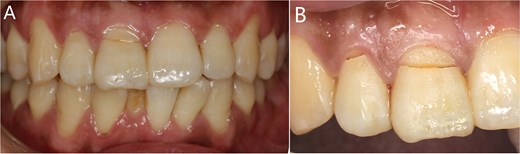

The patient fell down the stairs and injured his maxillary anterior teeth one day before (Fig. 1).

(A) The whole teeth photograph; (B) The fracture lines in teeth 11 and 12.

Midline smile line; gingivitis with bleeding on probing; absence of occlusal interference. Severe percussion pain (+++) was observed in teeth 11 and 12. Teeth 11 and 12 exhibited crown fracture with grade-III mobility of the fractured segment.